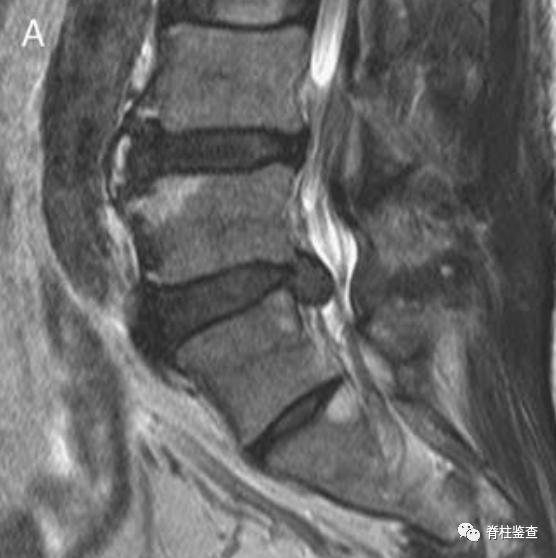

术后减压良好,硬膜囊再扩张(白色↓)。